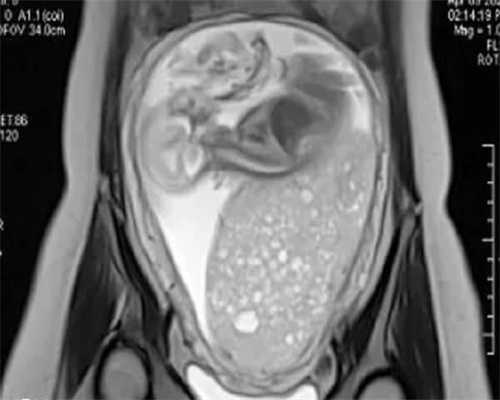

黄体酮热敷对胚胎没有影响 黄体酮又称孕酮,是一种天然孕激素,具有保护胎儿的作用,如果女性孕酮过低,很容易出现异常出血,从而导致流产,这时就需要打黄体酮来提高女性孕酮水平,保护胎儿和胎儿。服用黄体酮后,臀部会有硬块,热敷硬块,只能促进臀部血液循环,对胚胎不会有任何影响。

移植后的黄体酮主要是因为服用试管婴儿毕竟是人为因素,而且体内的激素水平并不会出现增加的现象,有可能会因为黄体酮过低而增加流产的发生,所以在这个阶段可以提升黄体酮的价值,起到安胎的作用。而且因为黄体酮注射液是一种油剂,肌肉注射药物不能马上吸收,一般会出现注射部位疼痛、硬块等症状,所以这需要可以通过热敷的方式来缓解。